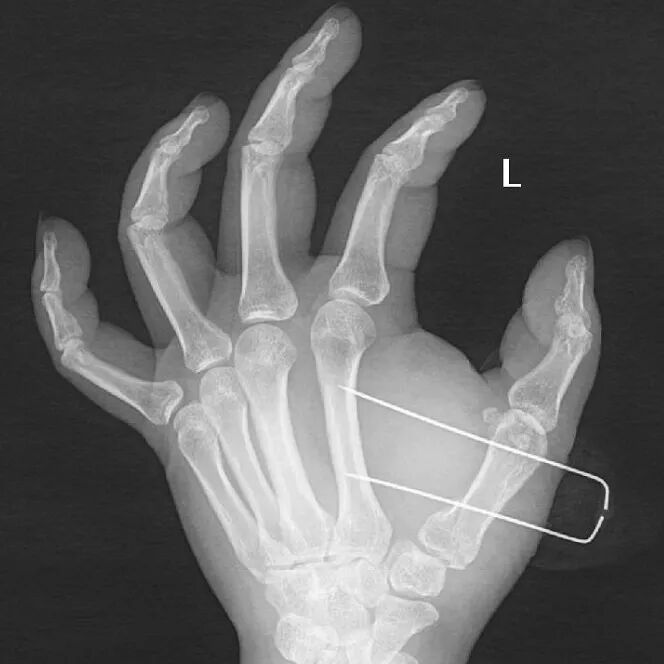

患者是39歲男性,因摔倒導致左手第一掌骨基底部骨折。

手術前左手正斜位片

手術后次日復查左手正斜位片